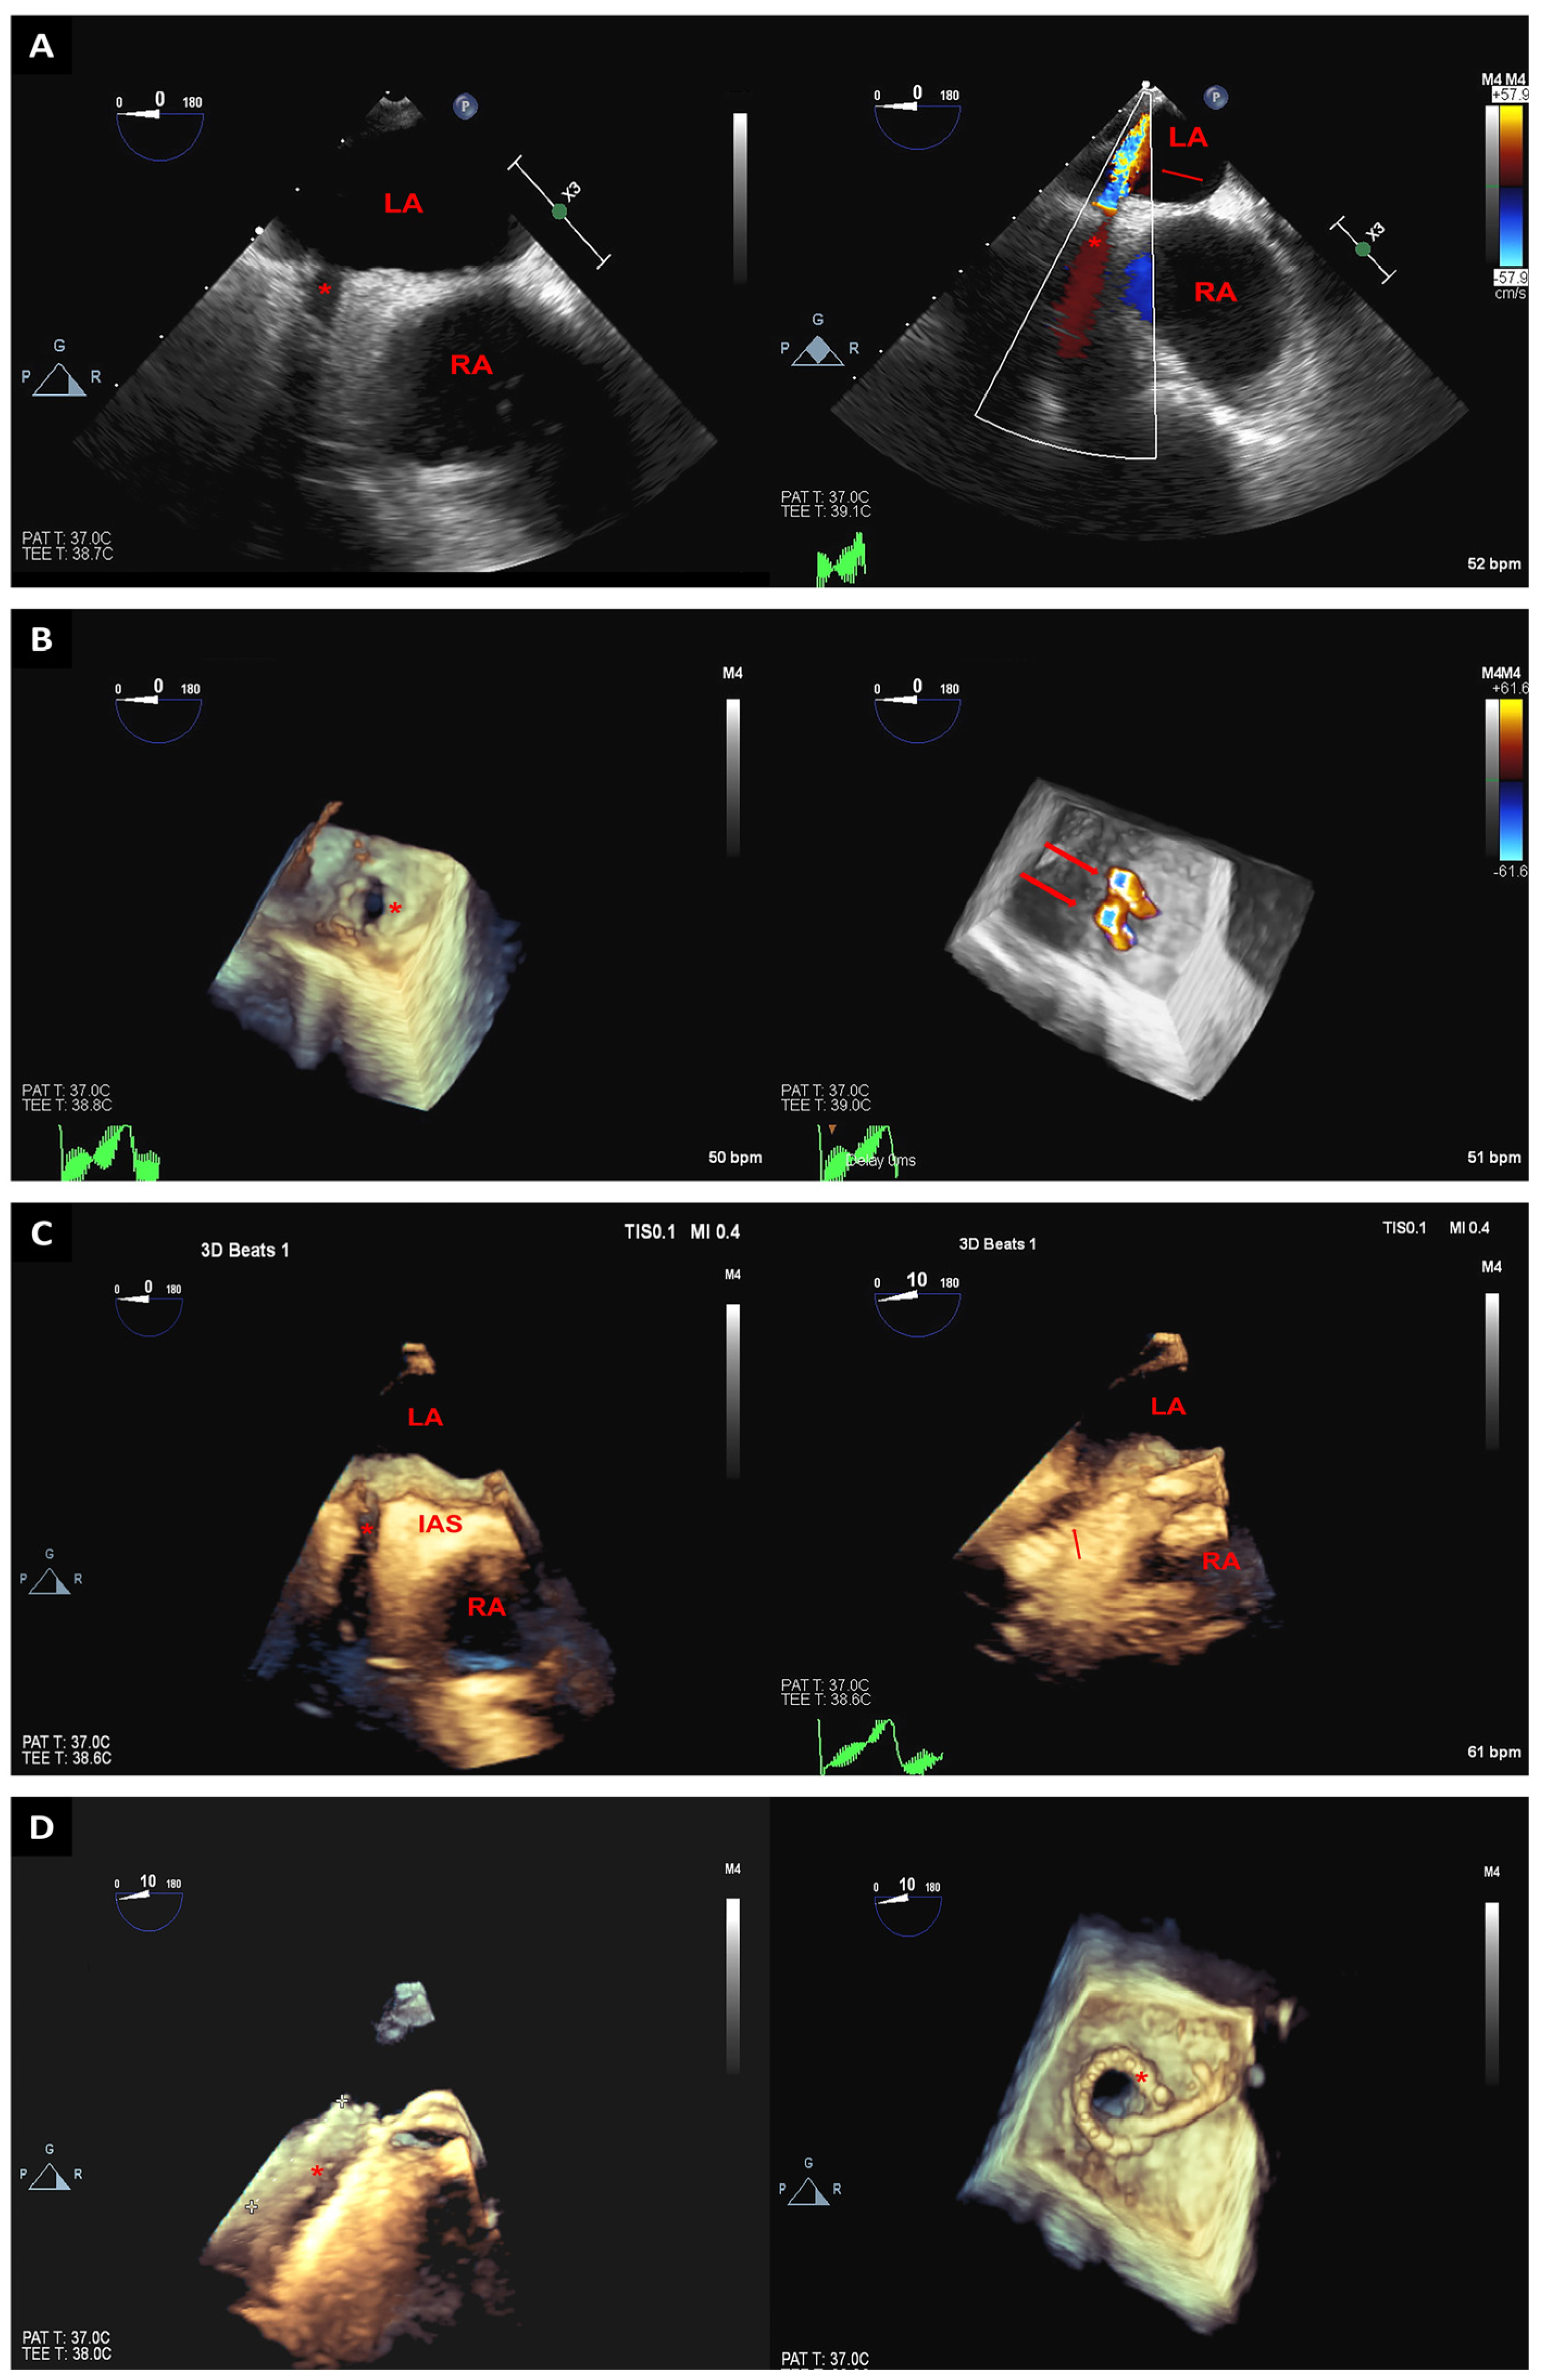

2. Trans-Septal Puncture

3.5. Left Atrial Appendage Closure